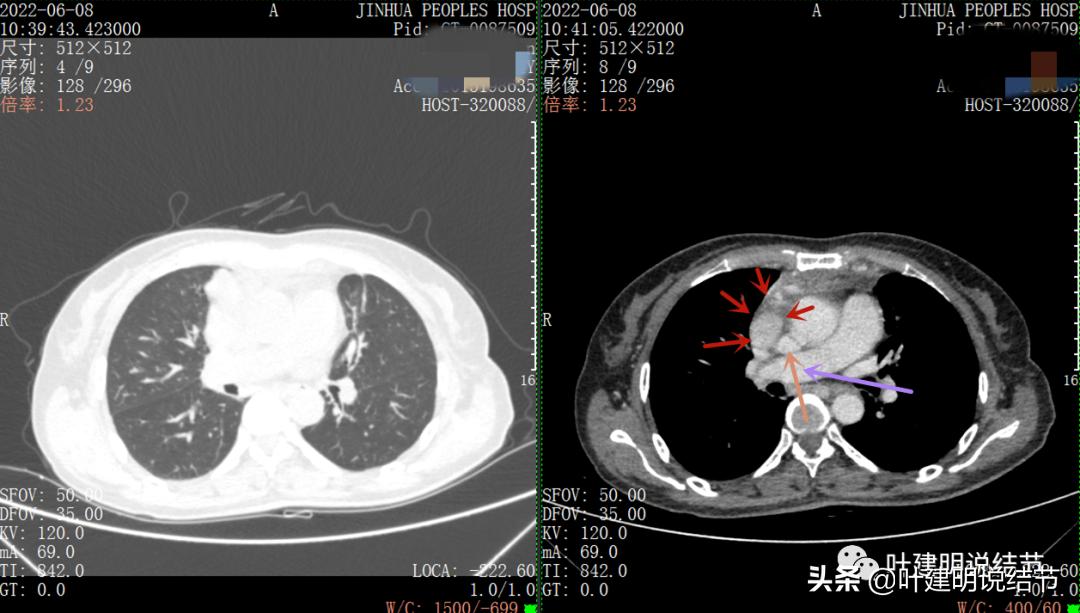

再来看看她的CT增强图像:

以下图片左侧是肺窗,右侧是纵隔窗。红色箭头示病灶,桔色箭头示无名静脉,黄色箭头示支气管,砖色箭头示上腔静脉,蓝色箭头示主动脉,紫色箭头示肺动脉。

病灶纵隔胸膜侧非常光滑,说明来源于纵隔

粉色箭头示淋巴结可能